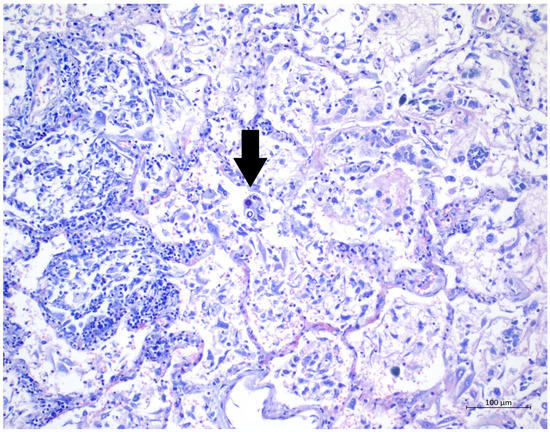

Figure 4. (Alcian blue, 20×) Special staining highlighting the mucous capsules.

A 60 year old male smoker with a history of arterial hypertension and myocardial infarction developed typical COVID-19 symptoms in April 2021—cough, exertional dyspnoea, chest tightness, and fever. Developing prior to the widespread availability of antiCOVID-19 vaccines, he was unvaccinated. Four days after the onset of symptoms, he was admitted to the Pulmonary Department of the University Hospital Brno due to the worsening dyspnoea. He tested positive for SARS-CoV-2. The exact viral variant was not identified. The predominant variant in the Czech population was B.1.1.7 (Alpha) at that time. His initial chest X-ray revealed diffuse lung infiltrates, especially in the right upper-middle quadrant. Despite receiving standard treatment with remdesivir for five days, corticosteroids (methylprednisolone 80 mg intravenously per day), and a prophylactic dose of low-molecular-weight heparin (LMWH), his dyspnoea worsened. Hence, supplemental oxygen and antibiotics (i.e., clarithromycin 500 mg IV BID and ceftriaxone 2 g IV BID for 5 days) were administered. Due to the progressively increasing levels of D-Dimers in laboratory tests, CT angiography was performed, showing typical findings consistent with COVID-19 pneumonia of diffuse lung parenchyma involvement without any signs of pulmonary embolism (Figure 1). The patient’s oxygen was gradually increased to achieve a peripheral blood saturation of >90%. On day 11, the patient was transferred to the ICU after his saturation dropped to 50–60% despite an oxygen flow via face mask of approximately 15 litres per minute. High-flow oxygen therapy (HFOT) with awake prone positioning was commenced, and corticosteroids were switched from methylprednisolone 80 mg to dexamethasone 6 mg IV per day. Despite ten days of corticosteroid administration, the patient’s clinical condition began to deteriorate significantly, and his hypoxaemia worsened. On day 12, he was intubated and placed on invasive ventilation with aggressive parameters (positive end-expiratory pressure: 12 cm H2O; fraction of oxygen: 80%). Bronchoalveolar lavage (BAL) was performed with the PCR testing showing more than 2 million copies of SARS-CoV-2 per millilitre (a significant number); no fungal DNA was detected at this time. As the patient became anuric, daily dialysis treatment commenced on day 13. Ventilator-associated pneumonia (VAP) caused by Klebsiella pneumoniae producing extended-spectrum beta-lactamase (ESBL) was confirmed by BAL fluid cultivation, and meropenem 2 g per day in continuous infusion was started. Serum levels of cardiac markers were elevated (troponin T: 67 ng/L; NT pro Brain Natriuretic Peptide (NTproBNP): 3892 ng/L), indicating advancing myocardial injury. Norepinephrine infusion was needed to achieve adequate blood pressure. The capillary refill time was prolonged over 2 s, consistent with circulatory dysfunction. A day later, the patient developed atrial fibrillation and hemodynamic instability with doses of norepinephrine up to 0.5 µg/kg/min. On day 16, a tracheostomy was performed, while the ventilation remained fully controlled with a P/F (PaO2/inspiration fraction of O2) index below 150. Two days later, the progression of circulatory dysfunction became apparent, accompanied by an elevation of inflammatory markers. Follow-up BAL was performed, empirical vancomycin was added on day 19, and doses were adjusted respecting dialysis procedures. Abdominal ultrasound revealed no clear site of a new infection. Blood cultures were negative, and BAL showed more than 3 million copies of SARS-CoV-2 and 1200 copies of Cryptococcus neoformans per millilitre/BAL. Serum panfungal antigen ((1,3)-β-glucan D) and serum cryptococcal antigen (i.e., glucuronoxylomannan) levels were negative. Over the next four days, organ dysfunction slightly improved; therefore, the patient was slowly weaned-off sedation, and the mode of ventilation was switched to pressure support. On day 21, vancomycin was switched to linezolid 600 mg IV BID. On day 22, a follow-up BAL was performed. PCR showed borderline positivity for Cryptococcus neoformans (300 copies per millilitre), and serum positivity for cryptococcal antigen was detected. Combined antifungal therapy with liposomal amphotericin B (Abelcet) 500 mg IV per day and fluconazole 800 mg IV per day was commenced. Blood cultures were negative for bacteria and fungi. Cerebrospinal fluid analysis, including PCR, ruled out CNS dissemination. On day 24, the patient’s circulatory instability progressed rapidly with no response to vasopressors and inotropes, which led to a subsequent cardiac arrest followed by unsuccessful cardiopulmonary resuscitation (CPR). Multiorgan dysfunction caused by COVID-19 infection and cryptococcal pneumonia was stated as the primary cause of death from a clinician’s perspective. The most significant feature during the histopathological examination was the severe diffuse alveolar damage (DAD) (Figure 2), specifically its exudative/proliferative stage, due to the prolonged period of COVID-19 pneumonia. In addition, a considerable number of dispersed intra-alveolar microorganisms, with a thick mucus capsule, were found in the lung parenchyma (Figure 3). These microorganisms (variably sized: approximately 7–20 μm) stained with both Alcian blue (Figure 4) and Giemsa (Figure 5). There was only a very subtle inflammatory reaction in the surrounding tissue, mostly lymphocytic. A post-mortem lung smear was microbiologically tested and returned positive for Cryptococcus neoformans. Thus, we consider secondary lung cryptococcosis as proven. Respiratory failure as a result of DAD was the immediate cause of death of the patient.